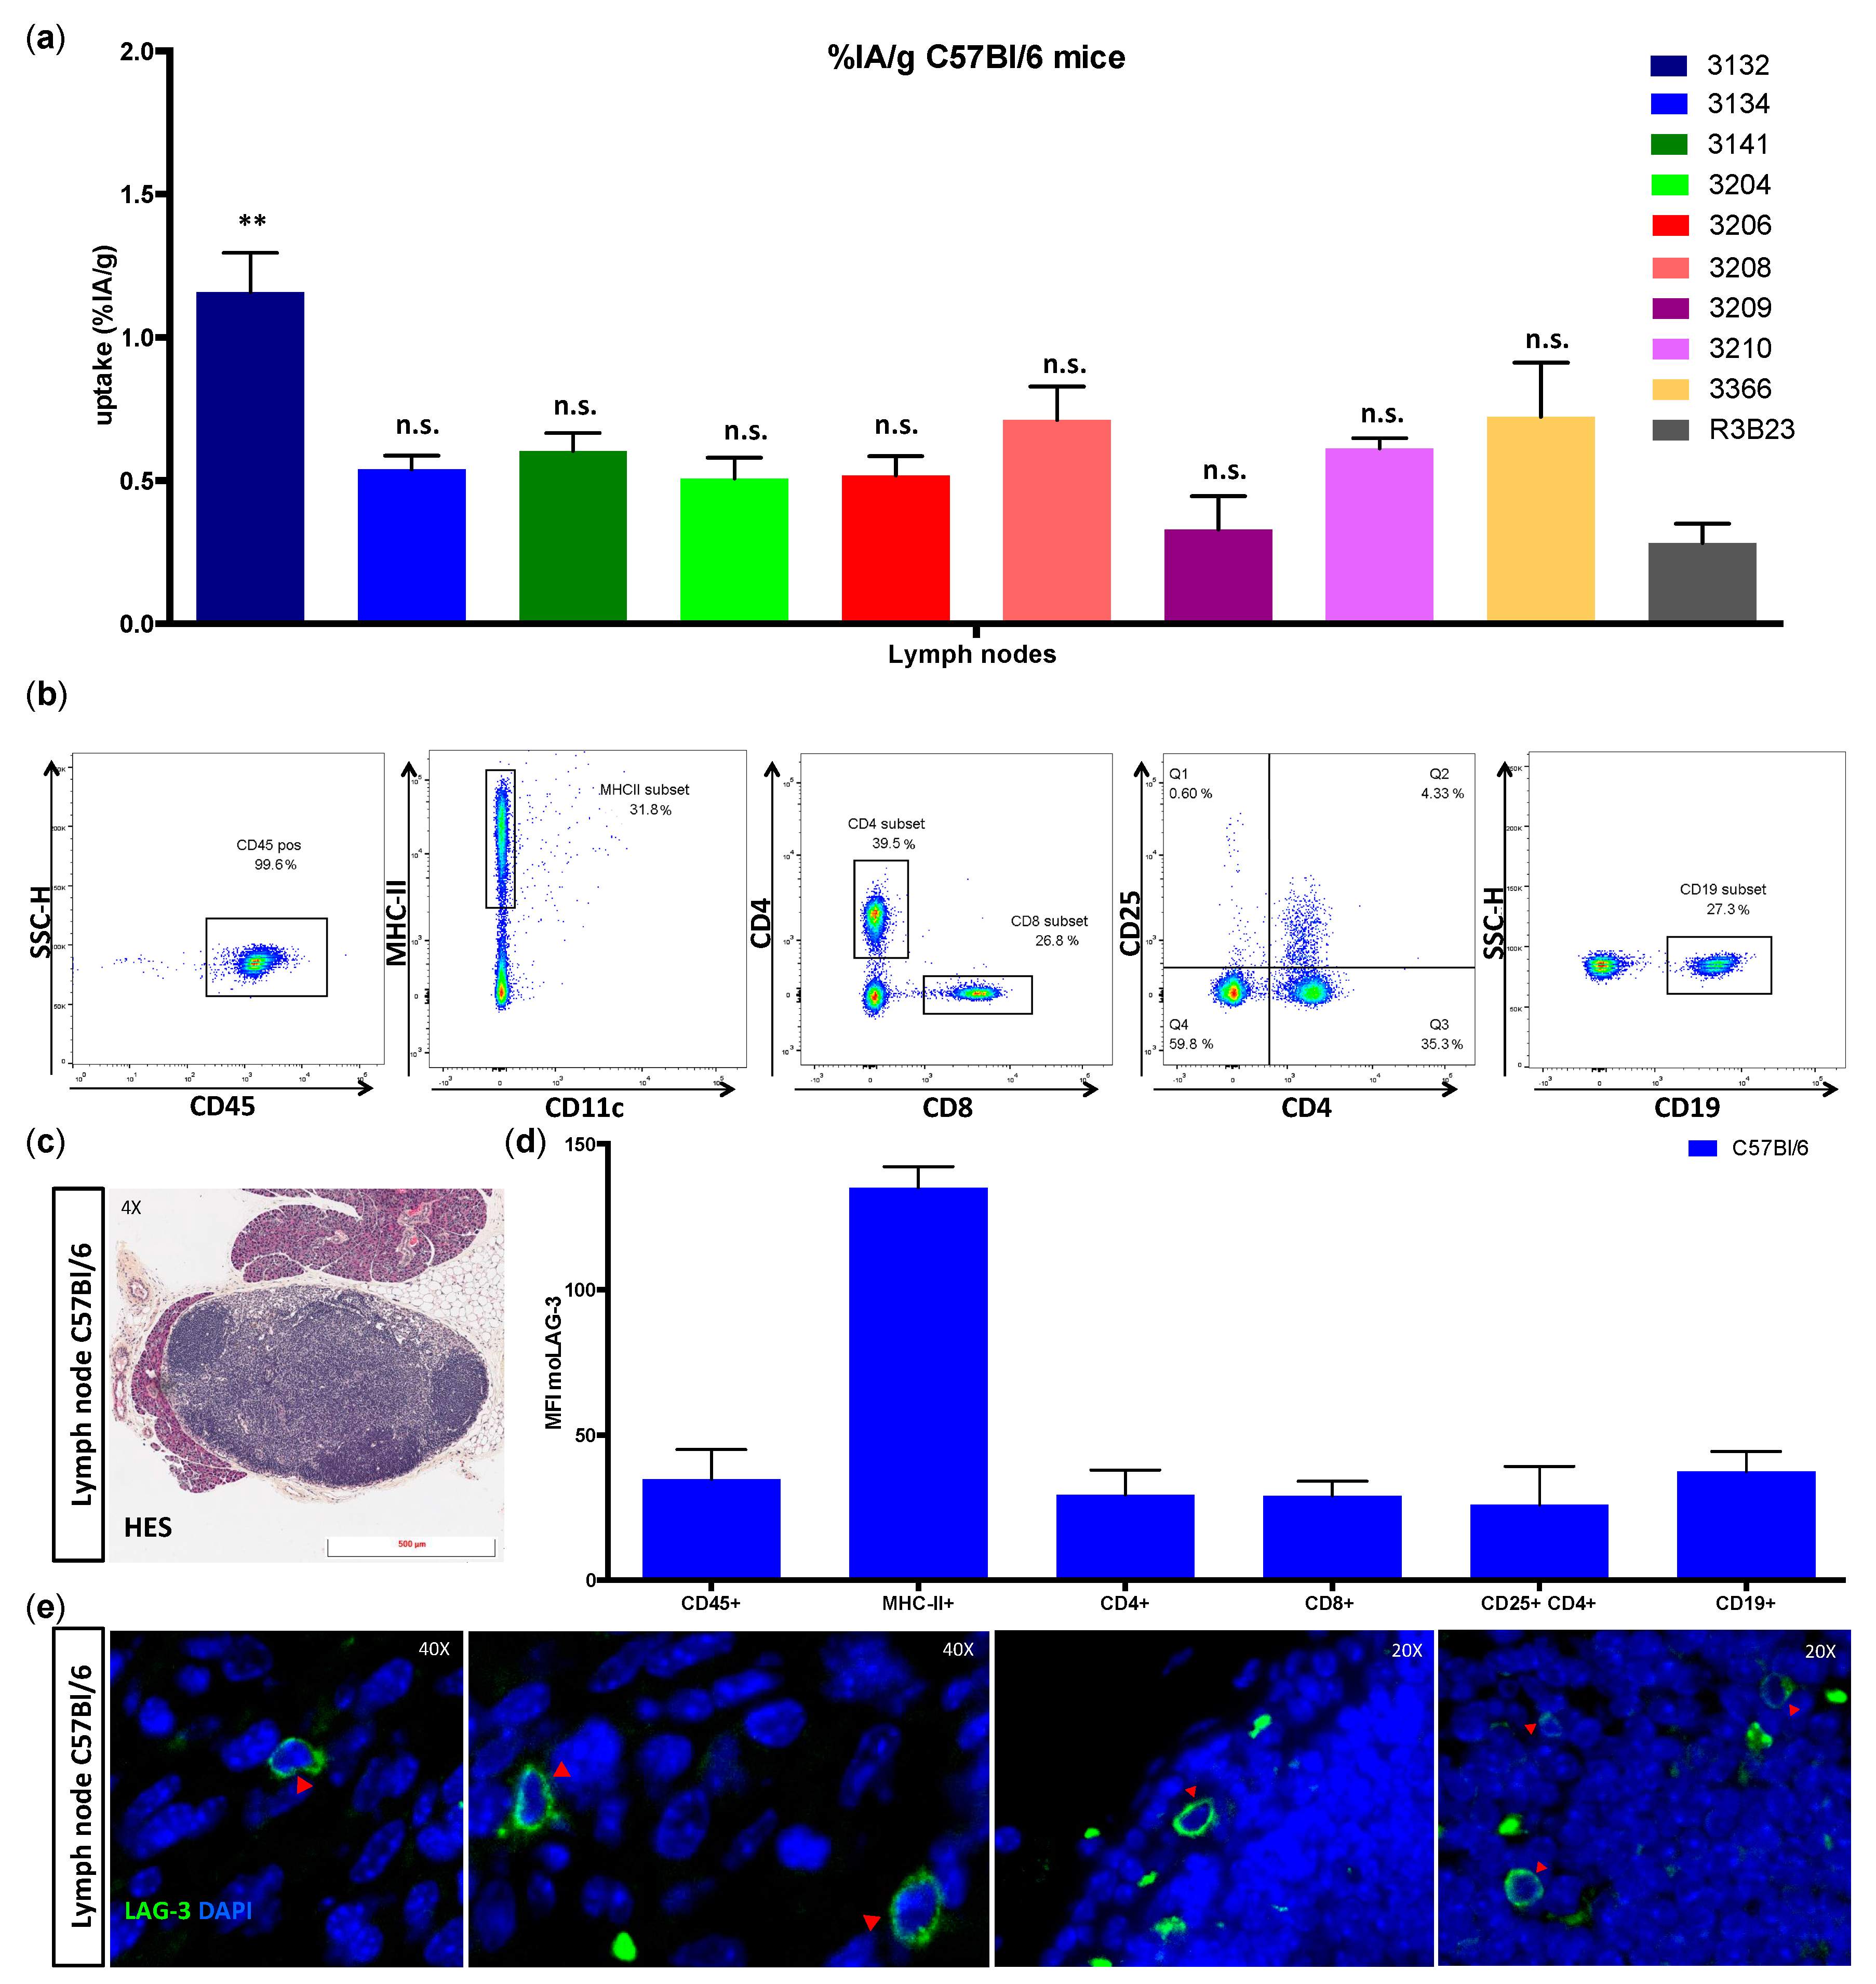

We showed that lymphocytes, residing in the lymph nodes of naive and healthy C57BL/6 mice, express low levels of moLAG-3. In contrast, lymph node residing antigen presenting cells expressed higher levels of moLAG-3. Within the spleen, the immune cell population (CD45

+) with the highest moLAG-3 expression could be detected on antigen-presenting cells, like dendritic cells and macrophages, and on NK and NKT cells [

4]. Moreover, very low amounts of moLAG-3 are expressed on CD19

+ B cells, and CD4

+ and CD8

+ T cells, which is comparable to the low levels found on lymphocytes isolated from lymph nodes. Nevertheless, out of nine different

99mTc-labeled anti-moLAG-3 Nbs, Nb 3132 was still able to detect and visualize low levels of moLAG-3 expressing immune cells residing in the spleen and lymph nodes. Although the affinity of Nb 3132 for moLAG-3 is rather low, injection of